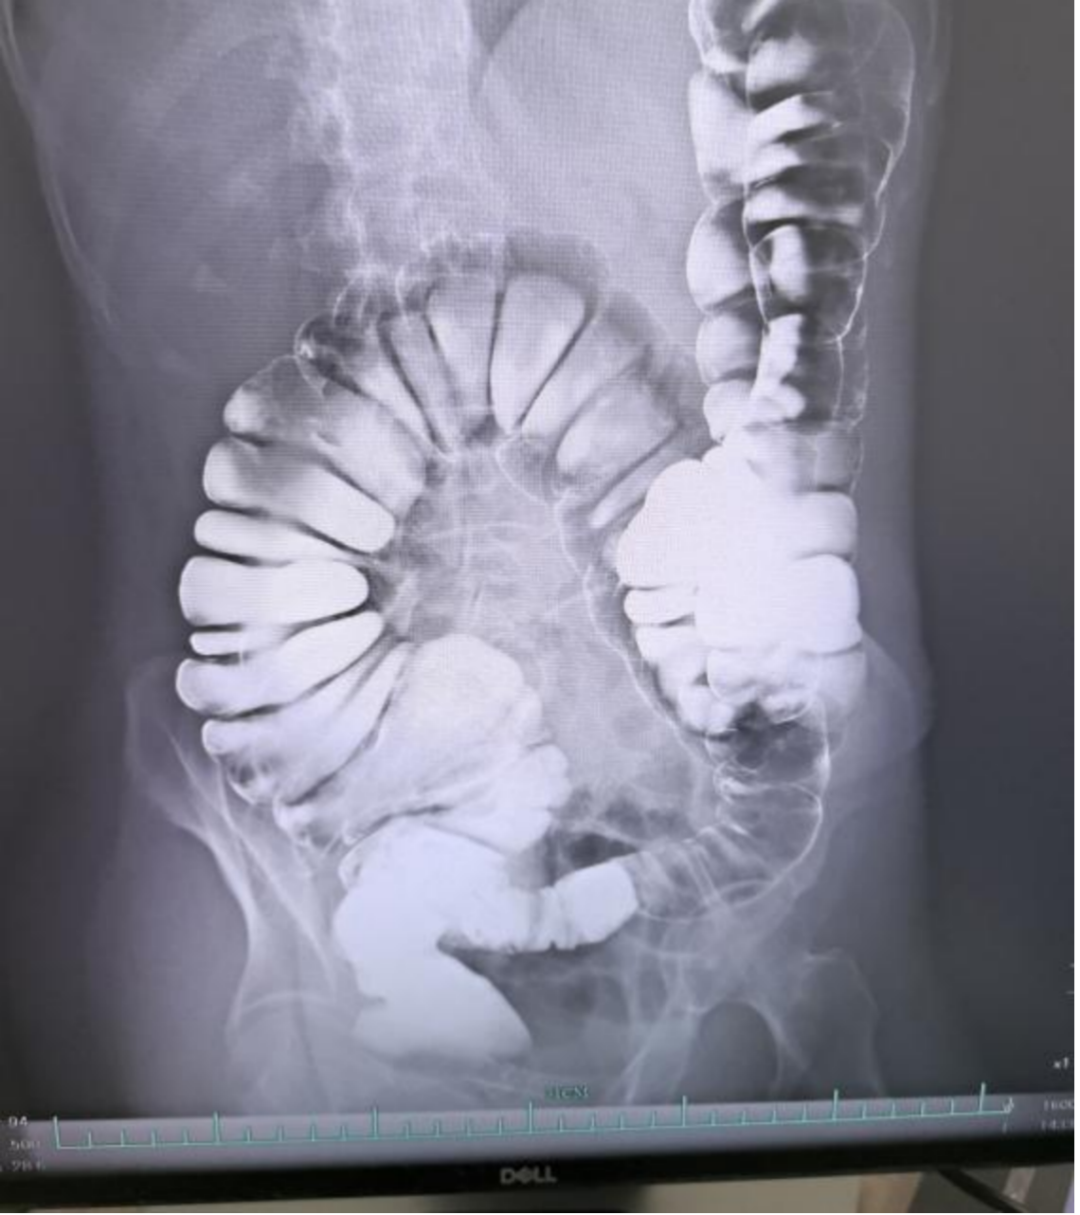

诊室里,浙大四院大肠外科王建伟主任医师的电脑屏幕上,一张结肠造影图堪称「壮观」。肠道蜿蜒盘踞,远远超出了一般人的长度。这是一位年轻高挑的李女士(化名)的检查结果,她长期被严重的便秘困扰。

王建伟主任打开电脑屏幕的结肠造影,图像清晰显示,她的结肠蜿蜒盘踞,像一条失去了弹性的松弛的长绳,部分甚至垂入了盆腔。